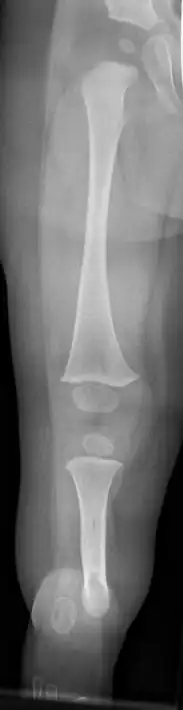

| Fibula hemimelia in patient affecting right side | |

Fibular hemimelia or longitudinal fibular deficiency is "the congenital absence of the fibula and it is the most common congenital absence of long bone of the extremities."[1][2] It is the shortening of the fibula at birth, or the complete lack thereof. Fibular hemimelia often causes severe knee instability due to deficiencies of the ligaments. Severe forms of fibula hemimelia can result in a malformed ankle with limited motion and stability. Fusion or absence of two or more toes are also common.[3] In humans, the disorder can be noted by ultrasound in utero to prepare for amputation after birth or complex bone-lengthening surgery. The amputation usually occurs at six months with removal of portions of the legs to prepare them for prosthetic use. The other treatments, which include repeated corrective osteotomies and leg-lengthening surgery (Ilizarov apparatus), are costly and associated with residual deformity.[4]

Partial or total absence of fibula is among the most frequent limb anomalies. It is the most common long bone deficiency and is the most common skeletal deformity in the leg. It most often is unilateral (present only on one side). It may also present as bilateral (affecting both legs). Paraxial fibular hemimelia is the most common manifestation in which only the postaxial portion of the limb is affected. It is commonly seen as a complete terminal deficiency, where the lateral rays of the foot are also affected. Hemimelia can also be intercalary in which case the foot remains unaffected. Although the missing bone is easily identified, this condition is not simply a missing bone.[2] Males are affected twice as often as females in most series.[5]